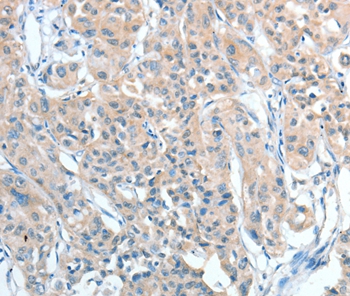

Immunohistochemical analysis of paraffin-embedded Human thyroid cancer tissue using #36058 at dilution 1/25.

Immunohistochemical analysis of paraffin-embedded Human lung cancer tissue using #36058 at dilution 1/25.